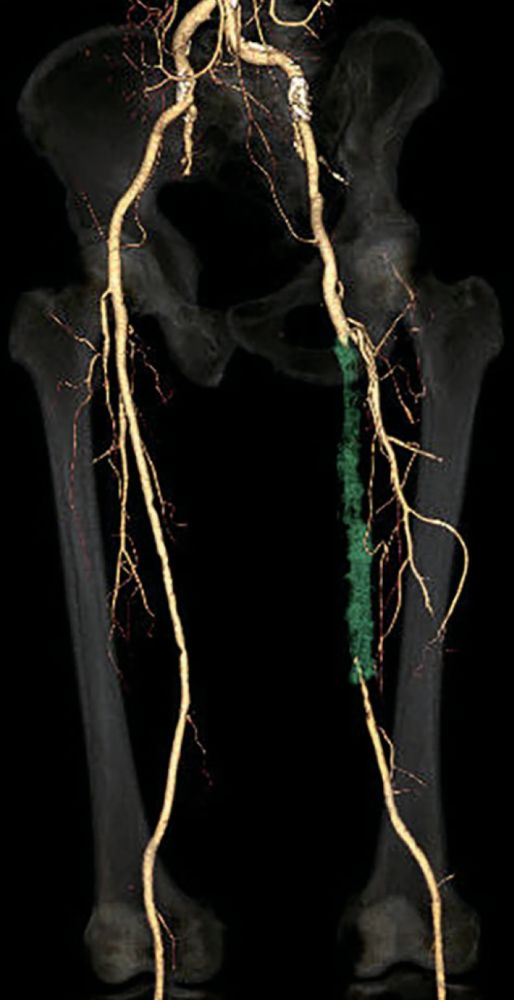

- 対象病変部位(図1): 左 SFA 閉塞(病変長約22 cm)

図1:術前